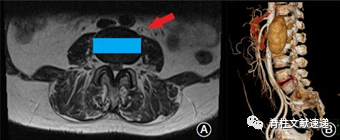

图示:(A)箭头表示到手术入路间隙,矩形表示cage的位置。MRI横截面决定了是否适合进行OLIF手术。(B) CTA检查是否有异常的血管畸形,降低血管损伤的发生率。